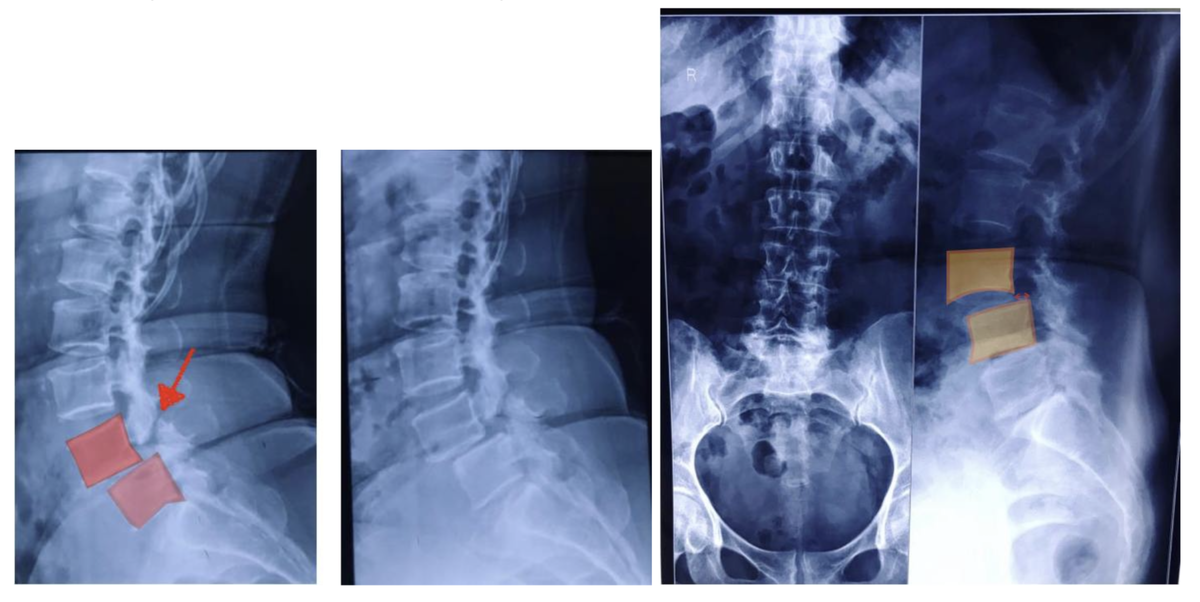

РСнтгСнография ΠΏΠ°Ρ†ΠΈΠ΅Π½Ρ‚Π° с истмичСским спондилолистСзом Π½Π° ΡƒΡ€ΠΎΠ²Π½Π΅ L4-L5.

Π‘Ρ‚Ρ€Π΅Π»ΠΊΠΎΠΉ ΡƒΠΊΠ°Π·Π°Π½Π° Π·ΠΎΠ½Π° ΠΏΠ΅Ρ€Π΅Π»ΠΎΠΌΠ° Π΄ΡƒΠΆΠΊΠΈ ΠΏΠΎΠ·Π²ΠΎΠ½ΠΊΠ° L4